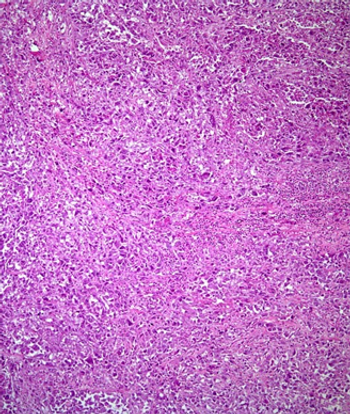

Oral agents and “watchful waiting” might make it possible to delay or avoid overtreatment with surgery and radiotherapy for many women diagnosed with ductal carcinoma in situ.

Not all DCIS is dangerous, and the prognostic genomic Oncotype DX DCIS Score allows for routine risk stratification of patients to avoid unnecessary treatment.